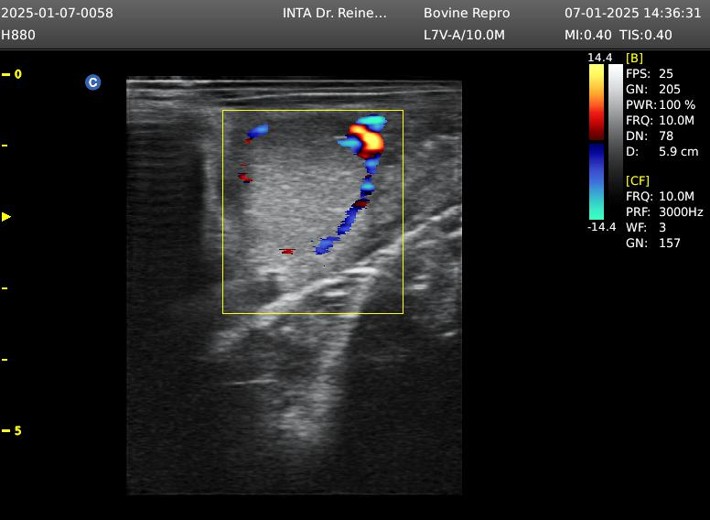

Generalmente, en rodeos comerciales, el diagnóstico del estado gestacional puede realizarse con precisión y de forma práctica a partir del día 30 posterior a la inseminación artificial, mediante la observación directa de la presencia o ausencia de líquido amniótico y del embrión en los cuernos uterinos. Más recientemente, se ha propuesto un método indirecto, utilizando ultrasonografía color, basado en la vascularización del cuerpo lúteo.

El cuerpo lúteo es una estructura ovárica encargada de sintetizar y liberar progesterona, hormona encargada de mantener la gestación. El equipo de profesionales del INTA Santiago del Estero y otros grupos de investigación, en otros trabajos ya publicados, describen que la disminución del flujo sanguíneo en el cuerpo lúteo podría indicar la aparición de luteólisis, relacionada con la ausencia de un embrión en el útero y, en consecuencia, la activación de vías apoptóticas que disminuyen la biosíntesis de progesterona. Por el contrario, una asociación positiva entre el flujo sanguíneo en el cuerpo lúteo y la concentración de progesterona es interpretada como un cuerpo lúteo activo.

Por lo tanto, la evaluación de la vascularización del cuerpo lúteo mediante ultrasonografía color puede considerarse una herramienta confiable para estimar la función lútea. Sin embargo, actualmente se utiliza un sistema de puntuación subjetivo para evaluar el área del tejido vascularizado y estimar la funcionalidad lútea, y hasta el momento no se habían desarrollado métodos objetivos, automatizados y rápidos, que relacionen la vascularización del cuerpo lúteo con el estado gestacional temprano, mediante estrategias de aprendizaje automático.